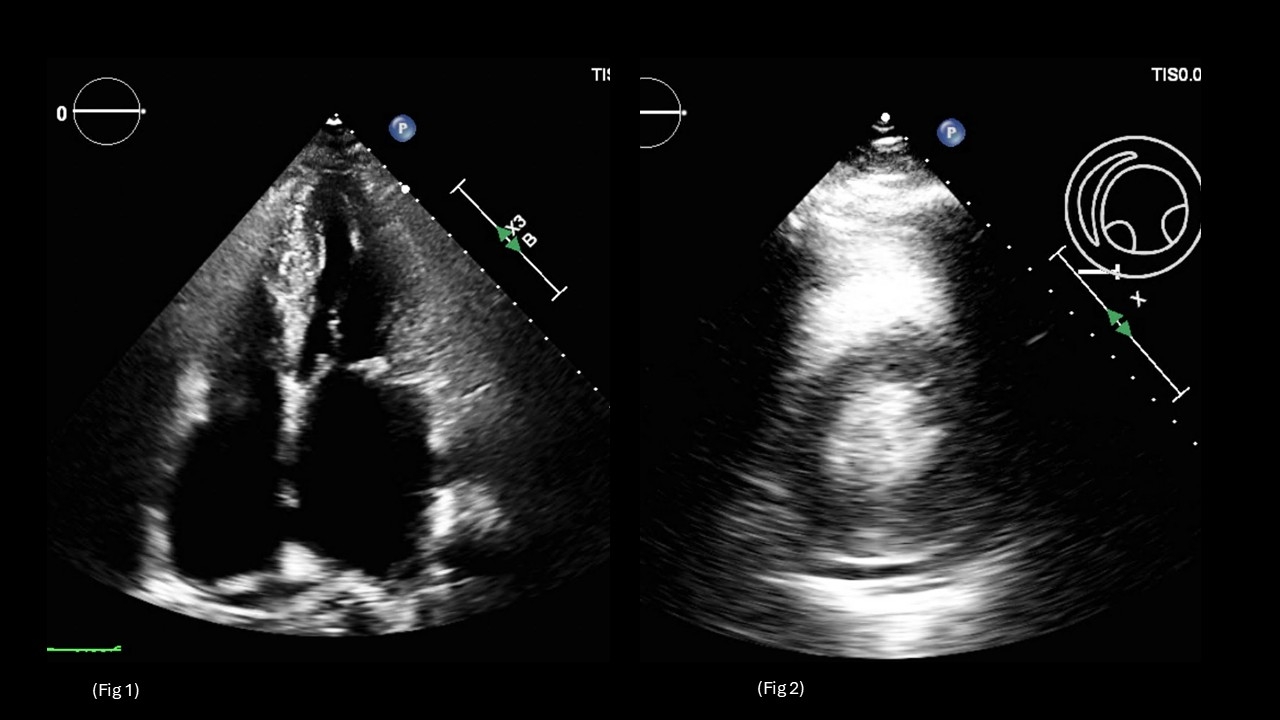

Cardiac MRI revealed severe asymmetric LVH with lateral wall thinning and a late gadolinium enhancement pattern with elevated extracellular volume, raising concern for an infiltrative cardiomyopathy (Fig 3a – Fig 3d). Over the next 4–5 months, the patient was readmitted twice for recurrent Afib with RVR, ultimately requiring catheter ablation.

Genetic testing identified mutations in both MYBPC3, consistent with sarcomeric HCM, and GLA, confirming Fabry disease. She was referred for endomyocardial biopsy and further evaluation for potential gene-targeted therapy.